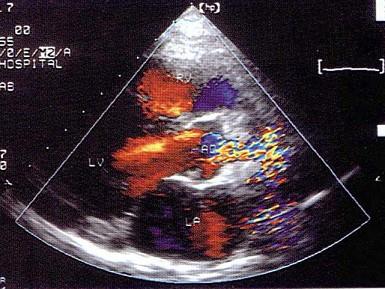

问题 该病例最可能的诊断?(?)

选项 A.高血压病 B.主动脉瓣上缩窄 C.主动脉瓣上膜性狭窄 D.瓣上环形狭窄 E.肥厚性心肌病

答案 B